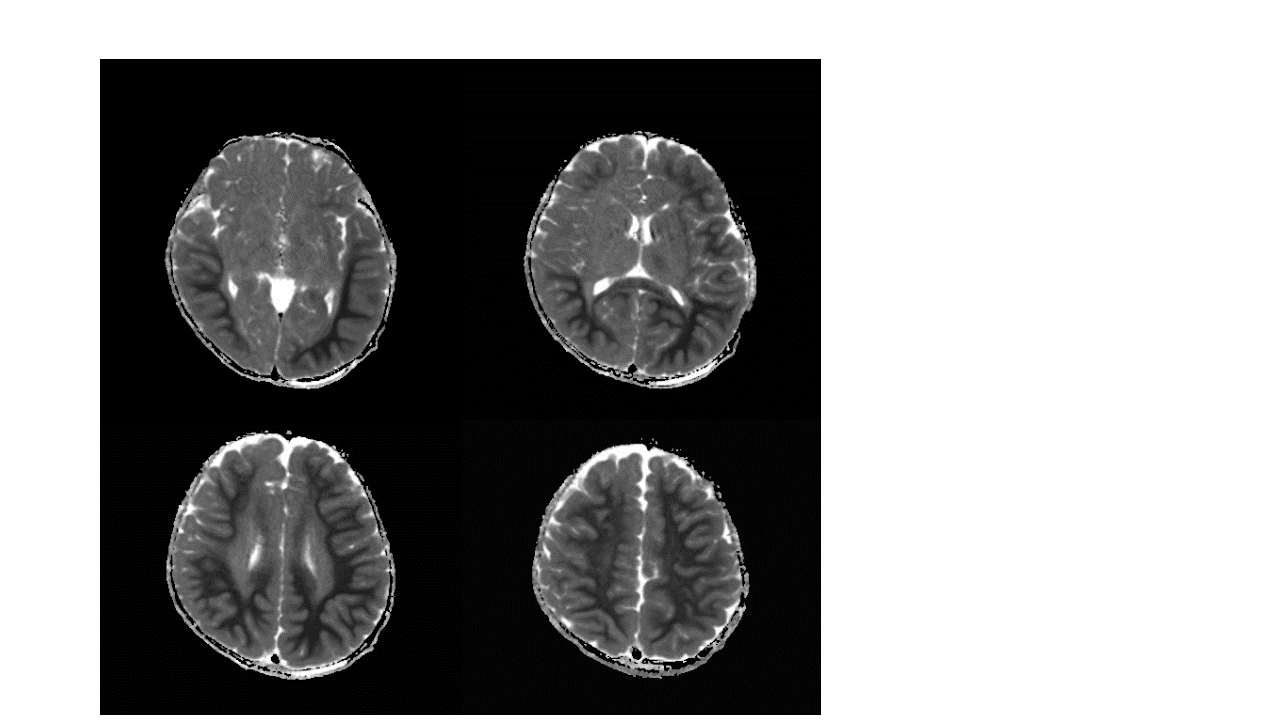

Symmetric areas of Restricted Diffusion in the bilateral temporal and parieto-occipital subcortical and periventricular white matter and in the bilateral frontal subcortical white matter. The white matter depicts a “bright tree appearance” which represents high-signal intensity on DWI B1000 in the subcortical white matter, akin to tree branches.

Areas of Restricted Diffusion are also seen in the leftthalamus, caudate nuclei bilaterally, dorsal pons, inferior cerebellar cortex in the paramedian location and in the superior vermis.

Subtle thickening of the cortex in the bilateral parieto-occipital regions with mild blurring of gray-white matter interface in these regions.

Imaging features suggest diffuse type Acute Leukoencephalopathy with Restricted Diffusion - ALERD